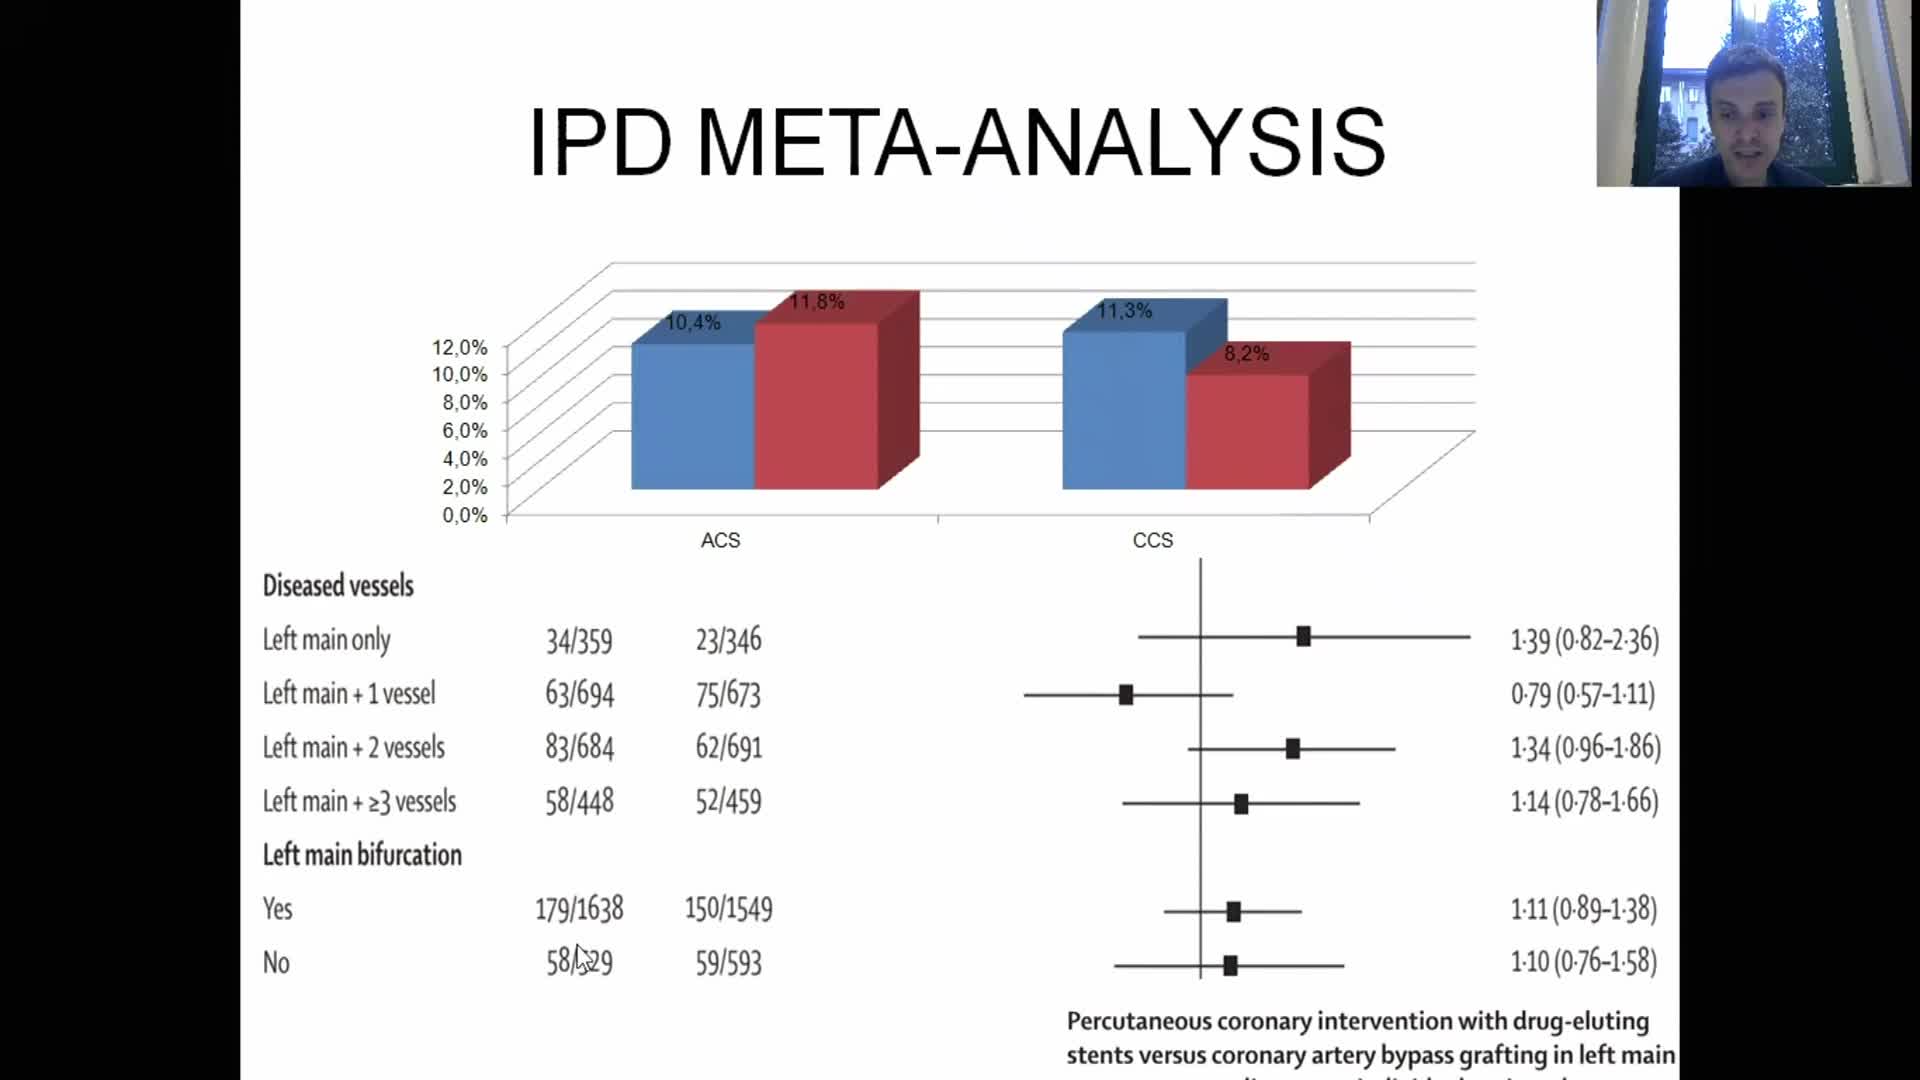

Spotlight Discussion: Management of multivessel disease in patients with acute coronary syndromes